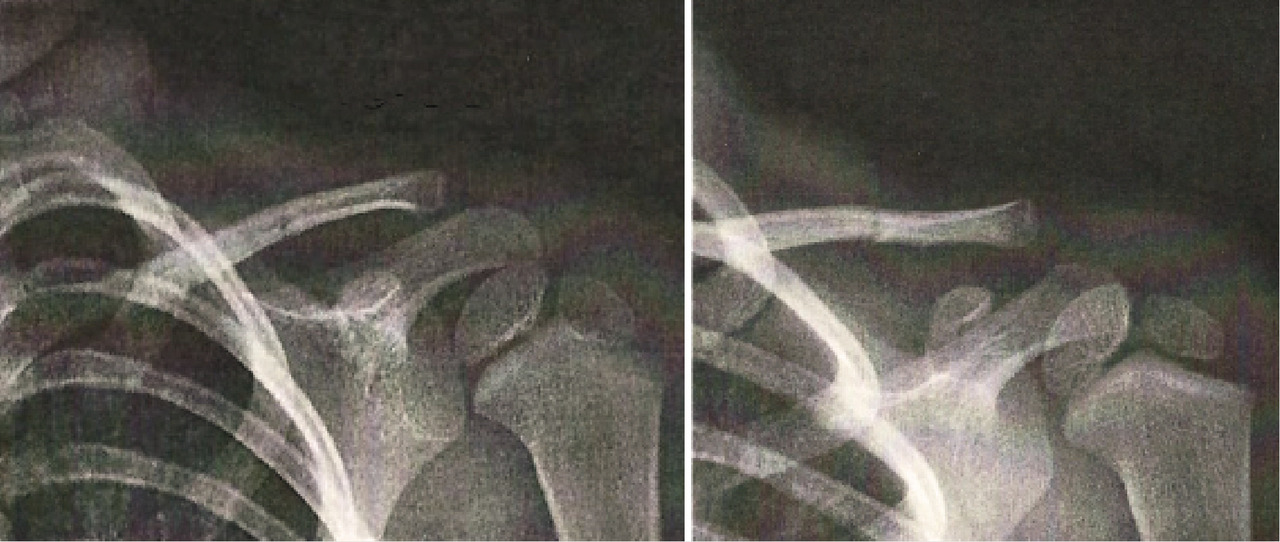

Le jeune Théo, 4 ans, consulte avec sa mère pour un défaut de mobilité du membre supérieur gauche apparu depuis quarante-huit heures. Lors de l’examen clinique, il lui est impossible de mobiliser le bras gauche en antépulsion ou en rétropulsion. Aucune douleur n’est par ailleurs relevée. Devant cette situation, une radiographie est réalisée (figure).

Le diagnostic est souvent porté tardivement car les parents ne prêtent pas nécessairement attention à un déficit léger, de surcroît non forcément exprimé par l’enfant. Il repose sur la réalisation d’une radiographie de l’épaule de face et d’un profil de Lamy, visualisant parfaitement la scapula.